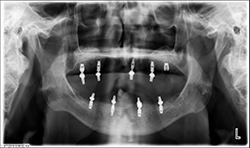

The patient’s medical history was evaluated for a mandibular fixed hybrid prosthesis using four Bicon implants and a TRINIA substructure. A CBCT revealed adequate bone for implantation and reviewed clinically after properly dissecting the mental nerve to avoid paresthesia. Four implants were placed through the anterior to increase the AP spread. Mandibular full thickness mucoperiosteal flap across the ridge was released and mental foramen were identified bilaterally. The posterior implant was placed 5 mm anterior to the mental foramen. All sites were prepared, checked for parallelism and enlarged to receive four implants each 4 mm x 8 mm with a 2.5 well (Fig. 4).

Fig.9

Fig.10

At a second appointment, four Bicon SHORT implants, three 4 x 6 mm and one 3.5 x 8 mm were placed in the mandibular arch (Figs. 9, 10). After normal healing time, both the maxillary and mandibular arches were fitted with a fixed hybrid prosthesis fabricated from a TRINIA substructure and Ceramage denture teeth. The patient was happy with the fit, function and comfort (Fig. 11).